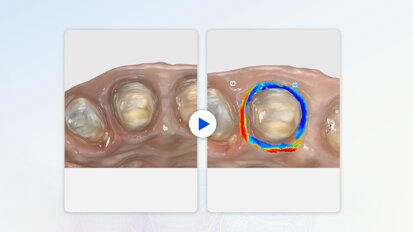

Bis heute ist nach Angaben von BZÄK und KZBV in Deutschland kein Infektionsgeschehen in zahnärztlichen Praxen dokumentiert, welches eine solche Empfehlung rechtfertigt. Die beiden Bundesorganisationen forderten Patienten und Versicherte einmal mehr auf, eine Versorgung durch Zahnärztinnen und Zahnärzte für den Erhalt und die Verbesserung der Mundgesundheit wahrzunehmen und nicht aus unbegründeter Angst vor Ansteckungen mit Corona zu verschieben. Andernfalls bestehe das Risiko, dass sich die Mundgesundheit durch das Entstehen von Karies, Zahnstein oder durch parodontale Erkrankungen unter Umständen dauerhaft verschlechtere und damit auch die allgemeine Gesundheit gefährdet.